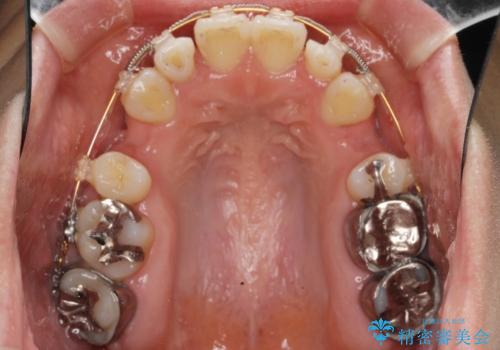

全顎的に歯並びにがたつきがあり、上の側切歯(上顎両側2)は生まれつき小さい歯(矮小歯)でした。

矯正治療後、矮小歯をセラミッククラウンにより理想的な歯の大きさに仕上げました。

※矯正治療は井上副院長が行っております。